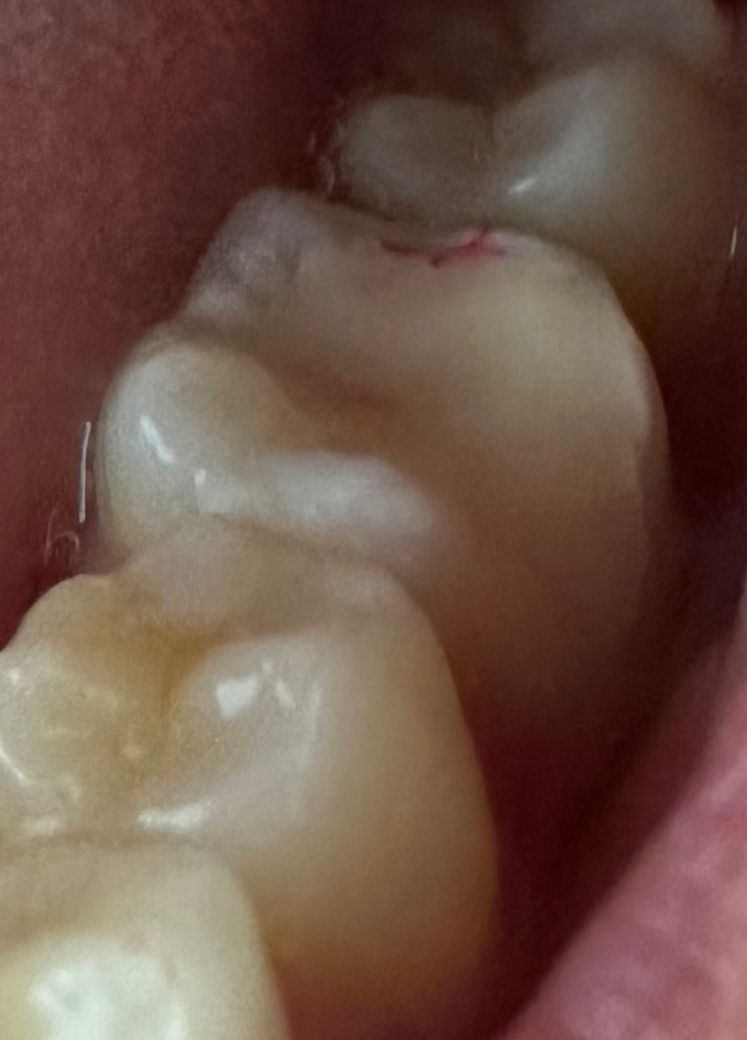

• 1번 째 사진

엑스레이로는 옆면 충치라 잘 보이지 않는다며 사진을 찍어 치아를 직접 보여주셨고 겉보기에는 작아 보이지만 파내 보면 클 수도 있다고 하셔서 일단 조금만 파보기로 했어요

그런데 실제로 파보니 생각보다 충치가 깊다고 하셨어요

다만 어제 넣어두었던 임시 재료를 치위생사분이 제거하는 과정에서 치아가 많이 갈린 것 같아 시린 느낌이 들었고 남아 있는 치아가 많지 않아 인레이를 할 경우 나중에 부러질 위험이 크다며 크라운 치료를 권유받았어요